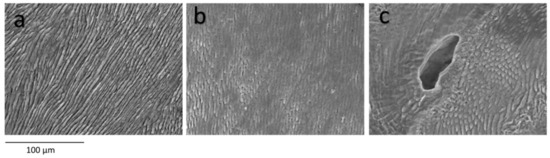

In the enamel, anomalies were found in 60% of the primary teeth of subjects with OI, in the form of interruption of the prisms and loss of the prismatic structure (Figure 1b) and inclusions of vesicles or ovoid formations inside (Figure 1c). Only in one tooth was the alteration severe, presenting an amorphous enamel, while in the remaining cases the alterations were between moderate and mild. Regarding the type of OI, the enamel alterations were very heterogeneous, with mild alteration being the most frequent in OI-I, while in OI-III and OI-IV the most frequent were moderate. The differences with the control group (Figure 1a) are statistically significant (p value < 0.001), but the differences between the OI types are not statistically relevant, although more severe enamel alterations are found in the more severe OI phenotypes (p value = 0.156).

Figure 1.

Enamel. SEM photomicrographs at 500× magnification (a–c). Enamel without morphological alterations, from a control tooth (a), enamel with alterations in the prismatic structure (b) and enamel with alterations in the prismatic structure and the inclusion of an ovoid structure inside (c).

In previous investigations in subjects with OI, no histological alterations in the enamel were found [10,17,29] and the tendency to fracture or detachment of the enamel is justified by the loss of the DEJ scalloping and the involvement of the underlying dentin. Despite this, Lindau [20] described alterations in the mineralization of the primary enamel, especially in cases of clinical DGI, although without finding differences between the different types of OI. On the other hand, some authors [30,33] established that, although the enamel is apparently normal, there are areas with fractured enamel prisms and an irregular trend of the enamel prisms and unpacked crystals of hydroxyapatite in all teeth. We found alterations corresponding to loss of crystalline structure, interruption of the lamellar pattern and amorphous regions of variable severity in 60% of primary teeth. In those teeth in which the anomaly corresponds to fractures of the enamel prisms, we cannot establish whether these have been caused by being supported by an altered dentin, or by a specific affectation of the enamel. Coinciding with Lindau [20], with our results we cannot establish a relationship between the systemic phenotype of OI and the alteration of dental enamel.